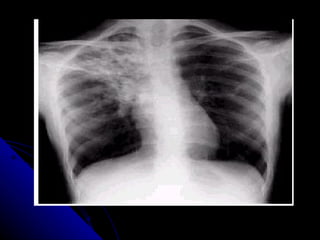

RADIOGRAFÍA DEL TÓRAX Es el registro en imagen fija, sobre una película expuesta a los Rx, que se obtiene en diferentes posiciones e incidencias: Frontal:  a.-PA    b.-AP c.-lordótica Lateral:  a.-derecha   b.-izquierda Oblicua:  Posición del nadador o boxeador.

RX TÓRAX TECNICAMENTE CORRECTA Se observa hasta la 6ta y7ma costillas Clavículas equidistantes Botón aórtico nítido Nivel de cámara gástrica Bordes y líneas nítidos Solo primeras vértebras dorsales visibles

Comprobar las cualidades técnicas de la Rx. Contraste (Densidades). Penetración. Adecuada inspiración ( se ven 6-7 arcos costales anteriores) Debe ser simétrica Los omóplatos no se deben proyectar en los campos pulmonares